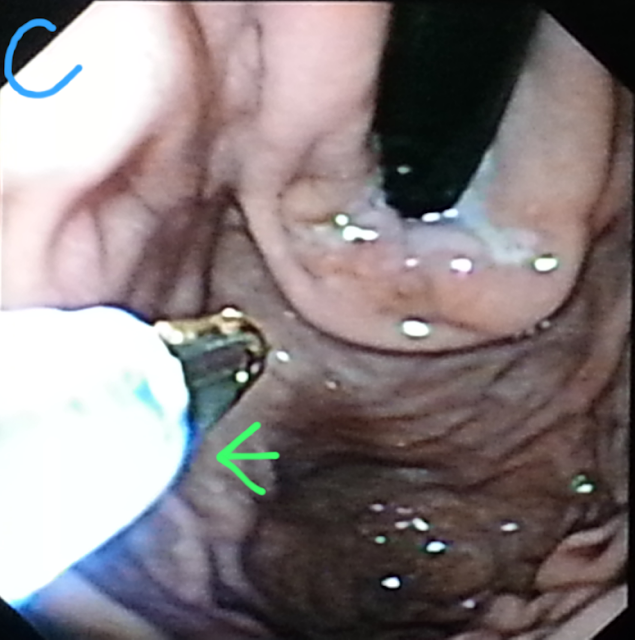

This 45 year old patient had been referred from another institution for balloon dilatation for achalasia of cardia. He had undergone an upper GI endoscopy and nothing unusual had been discovered. A barium swallow showed the classic bird beak lower esophagus (A: green arrow). The manometric findings also suggested classic achalasia. When we went in to dilate and retroflexed to view the fundus prior to wire insertion, the esophago-gastric junction was seen to be ulcerated and indurated (B:green arrow). We took biopsies (C: green arrow) and cancelled the dilatation till the biopsy report and a CT scan of the lower chest and abdomen.